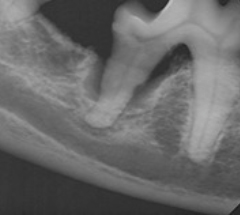

Tanncysteoperasjon

Av og til kan en ikke frembrutt tann lage en cyste i kjevebeinet. Derfor er det viktig at det tas tannrøntgenbilder av disse manglende tenner ved den første regelmessige munnhuleundersøkelsen. Slik cystebetennelse i kjeveben er meget alvorlig fordi mye beinsubstans blir borte og kjeven svekkes (se røntgenbilde). Under behandling vil den gjeldende tann bli fjernet, beinhulen renset og fylt. Det blir oppfølgings undersøkelse med tannrøntgenbilder. Rapport og veiledning til eieren.